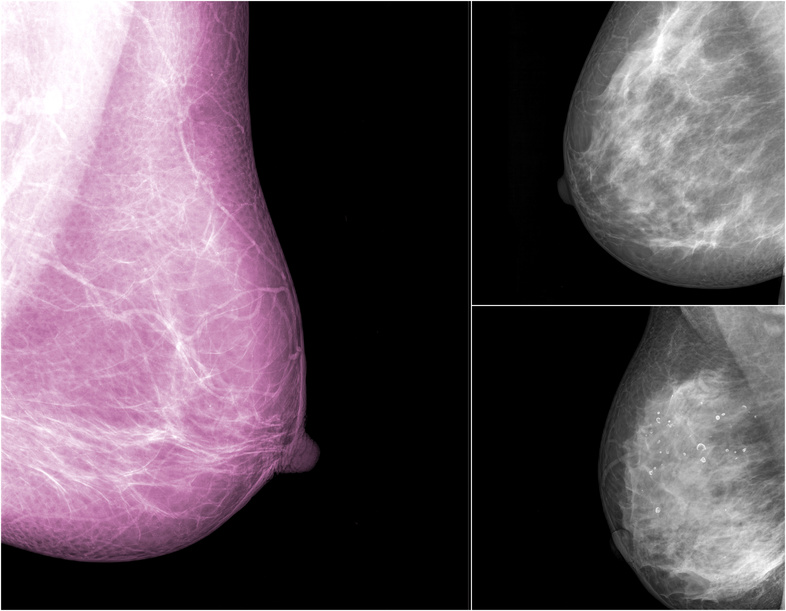

- Pregled dojki

(3D/4D UZV ), UZV dojki - Radiološka dijagnostika: MR dojki